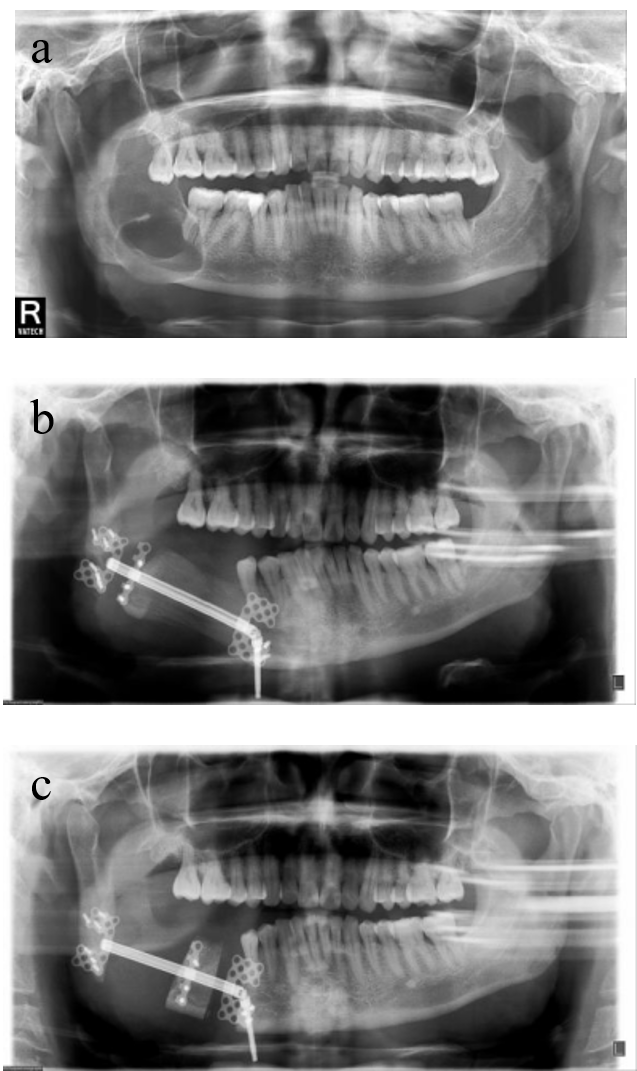

Figure 1. Surgical correction of maxillary retrusion with mandibular protrusion. a: preoperative frontal CT image. b: preoperative digital design and simulation. c: postoperative frontal CT image. d: preoperative lateral CT image. e: preoperative digital design and simulation. f: postoperative lateral CT image.